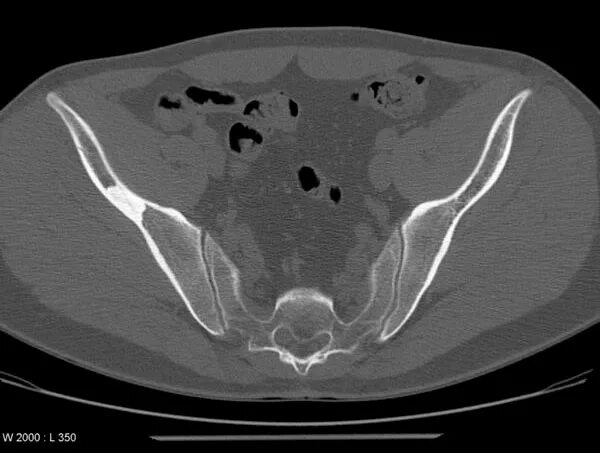

Что входит в мрт забрюшинного пространства